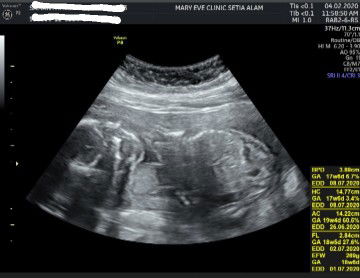

Siapa tahu ni baby boy ke baby girl??

Maaf sis sy hnye nmpk kpla dan bdn bby je..achnr sy nk bg jwpn😞maaf sbb xdpt mmbntu

kene celah peha baru tahu sis . ni 1 bdn mmg tk boleh agk

kalau ada gambar celah peha lagi clear boleh nampak

Gambar scan pun bukan tunjuk part gender 😅

Maaf, scan nya tak nampak jelas 😅